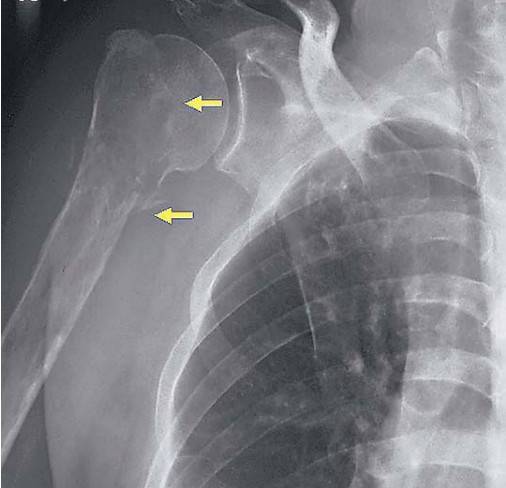

MM骨病变的检测手段主要包括X线、CT、MRI和PET/CT。X线的敏感性和特异性较低,目前已不作为MM影像检测的推荐。CT对脊柱、胸廓、骨盆的溶骨性病变的敏感性高于X线,能够更好的评估骨折风险和脊柱压缩性骨折的稳定性,CT在检测溶骨性病变方面比X线有更高的敏感性,但辐射较大。最近推出来的全身低剂量CT具有普通CT的高敏感性和特异性,且辐射较小,费用低,已逐渐成为患者的选择之一,但在国内该检测手段尚未广泛开展。

图1.X线显示MM患者的溶骨性病灶